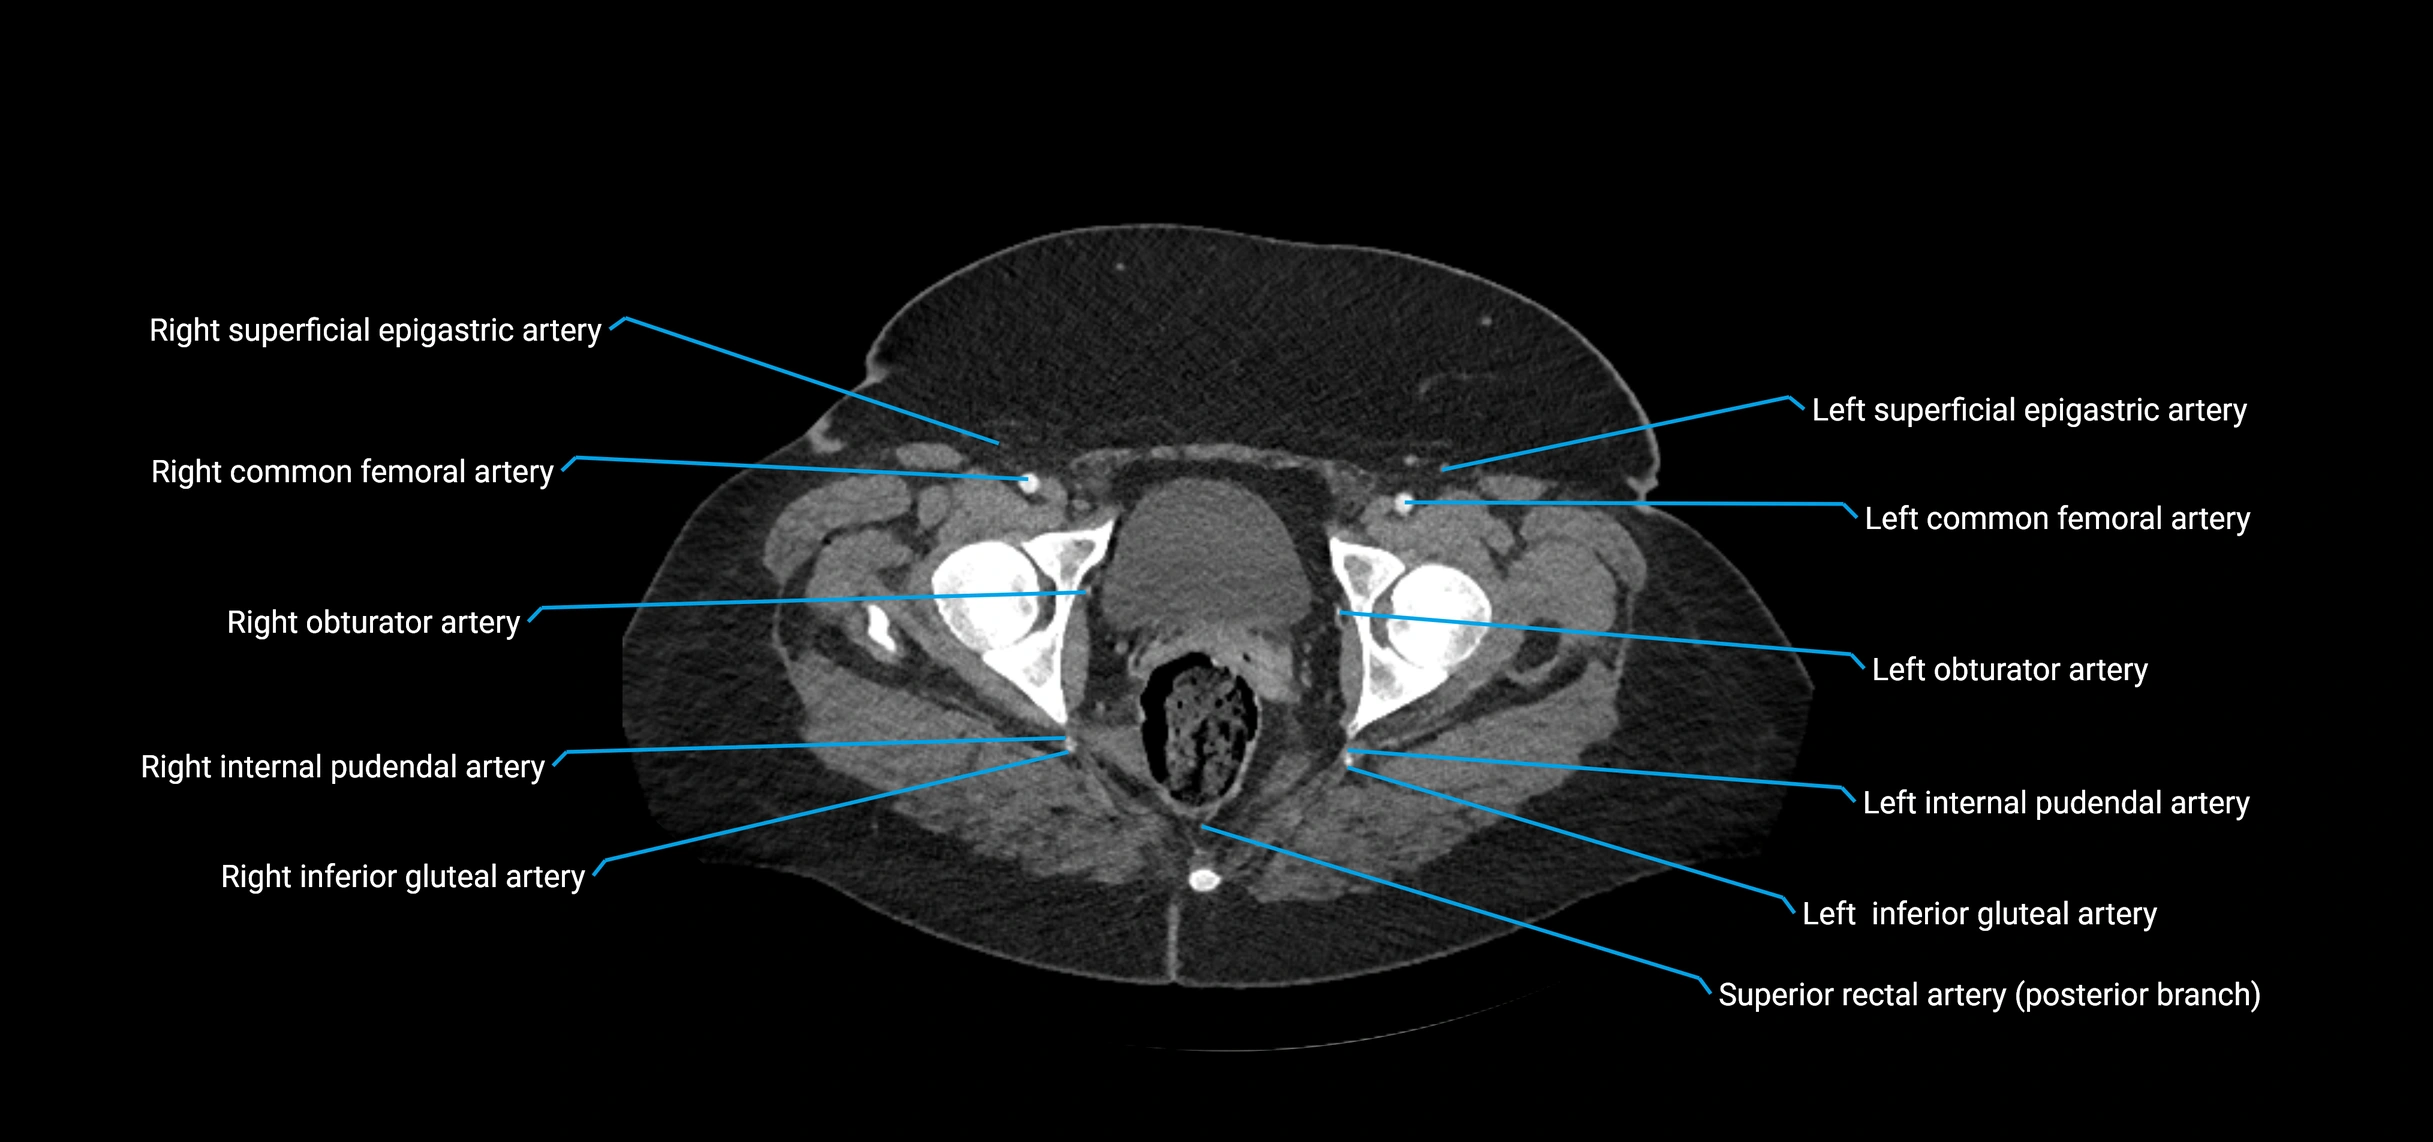

CT images

image

Contrast-enhanced CT (CTA):

• Gold standard for abdominal aortic imaging

• Provides excellent detail of lumen, wall, aneurysm, thrombus, and branch vessels

• Multiplanar and 3D reconstructions help in aneurysm measurement, stent graft planning, and dissection evaluation